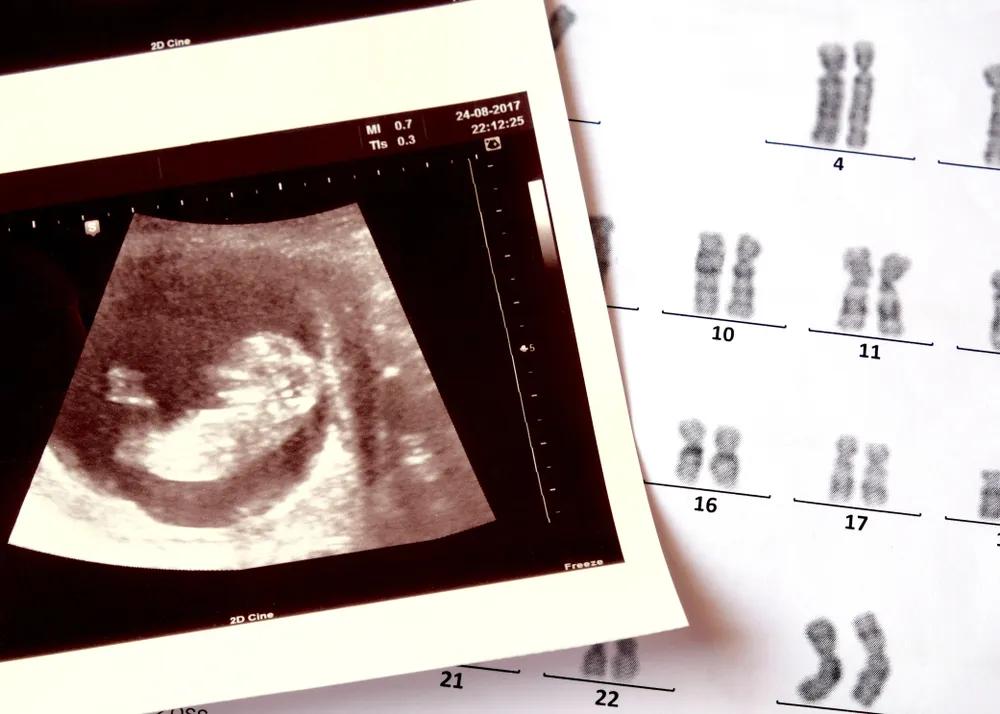

很多生育障碍的夫妇,寄希望于试管等生殖技术,来改变生活状态,但技术的不确定,让焦虑卷土重来,很多女性被身体受创与生殖焦虑反复拉扯。

为了尽可能排除那一点点因素,曾纪琪和黎晓都选了更明确的方案 —— 试管。

曾纪琪决定做试管之后,开始进入各种各样的试管群和求子论坛和不同的人聊天,她看到群里有不少人经历过四五次的、甚至有十几次还没有成功的,很多人是从安徽、苏北一些县和农村来到南京租房子做试管,最低费用的一代试管,一次也需要 4~5 万,很多人举债十几万仍未成功,她想给自己打个心理上的预防针。

医生让曾纪琪先促排卵,这意味着每一天她都必须早早地去医院打针、注射激素,再抽血查看激素水平;每一天都要去做 B 超,查看卵泡生长的情况;每一天都要屁股上打一针,肚子上打两针。算下来就是每一天至少要挨上三针,再加上一针抽血。

一关一关地过:等卵泡长到合适的时机,才到可以去取卵;取卵成功之后,要再等待卵子和精子结合成功,在这之后才能真正地进入移植期。